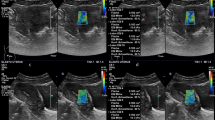

The position of the participants during ultrasonographic measurements, and the choice of the site for measurements on limbs were the same as those described in a previous study9. We measured the muscle thicknesses of the quadriceps femoris at the anterior aspect of the right leg using a real-time B mode ultrasound imaging device (Hi Vision Preirus; Hitachi, Tokyo, Japan) with a 7.5 MHz linear-array probe (EUP-L74M). To improve acoustic coupling without compressing the dermal surface, a water-soluble transmission gel was placed over the scan head. The transducer was held perpendicular to the skin surface. Images were captured, stored on the hard disk of the ultrasound machine, and then muscle thickness was measured using on screen calipers (Fig. 3). All measurements were performed with the participants in the supine position, meaning full extension (passively) at the knee and elbow joints. Mean muscle thickness was calculated as the mean of five consecutive measurements of each muscle site, and all measurements were performed by the same experienced investigator.

Ultrasonographic measurement sites on the rectus femoris (A) and vastus intermedius (B). Proximal point, on the anterior surface, 25% proximal to the point between the anterior superior iliac spine and upper pole of the patella; intermediate point, on the anterior surface midway between the anterior superior iliac spine and upper pole of the patella; distal point, on the anterior surface, 75% distal to the point between the anterior superior iliac spine and upper pole of the patella.